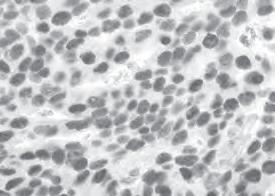

That total was enough for Hudson Institute to purchase a digital microscope with computer software that allows us to recognise and analyse cancer cells grown from patients.

The microscope, with a plaque in Jessica’s memory, was unveiled in late 2022 in the Centre for Cancer Research in a touching ceremony attended by the Lindner family.